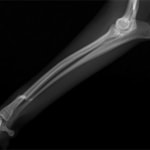

症例3:キルシュナーワイヤーのピンニングによる整復

ペルシャ猫 11ヶ月齢 雄

他院にて左大腿骨遠位の成長板骨折(salter-harrisⅠ型)が認められており、治療相談を目的として来院。当院にて、キルシュナーワイヤーを用いたピンニングにより骨折部位の整復を行いました。術後の経過は良好で、現在も経過観察中です。

術前レントゲン

術後レントゲン